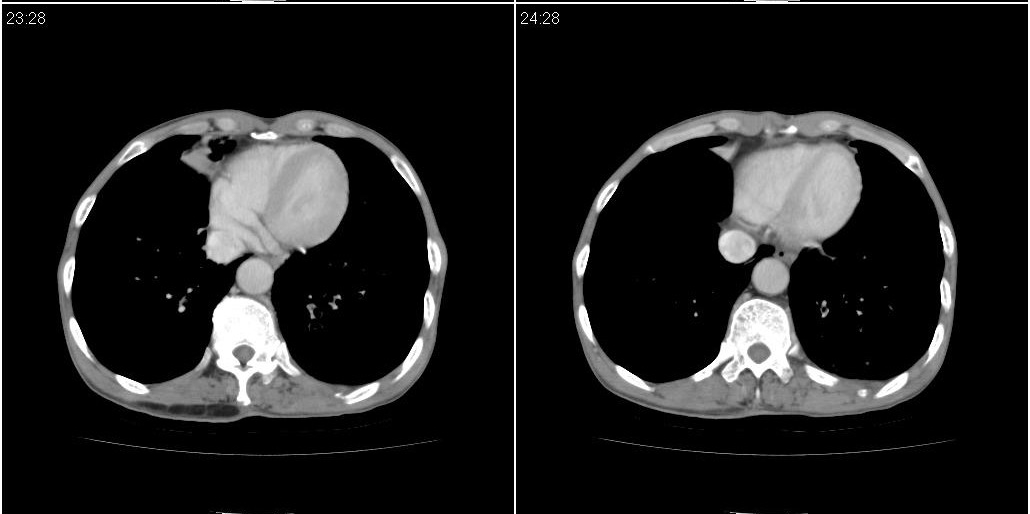

作者: lyb999 时间: 2010-3-31 04:52

1)右肺中叶慢性炎症并支气管扩张,节段性肺不张。2)左肺下叶支气管扩张

作者: 黑白光影 时间: 2010-3-31 23:34

1)右肺中叶慢性炎症并支气管扩张,节段性肺不张。2)两肺下叶支气管扩张。